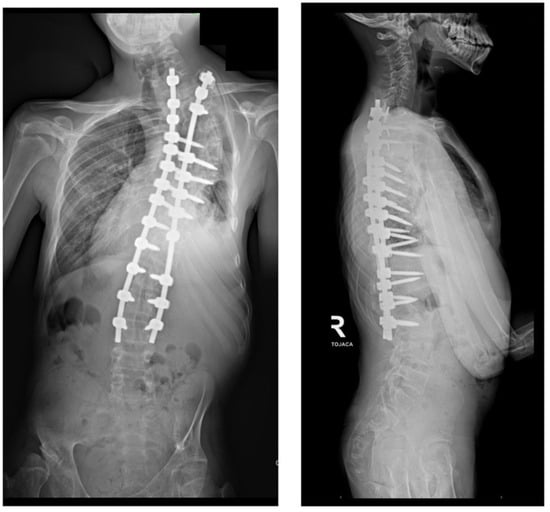

Figure 7.

Radiological standing X-rays AP and LAT of the patient with Costello syndrome at 2 years of follow-up after undergoing conversion from MCGR to posterior spinal fusion.

A 14-year-old boy was admitted to our clinic due to rapidly progressing scoliosis. He had previously been treated by other physicians and had an extensive history of conservative treatment of spinal deformities, including the use of a Cheneaux brace. Despite all the efforts made, the scoliosis continued to progress. During a visit to our clinic and examination, we revealed a spine curvature of 130 degrees (Figure 1 and Figure 2). The boy used a wheelchair due to severe walking problems. He was able to walk about 50–100 m on his own, but he developed pain in his spine and the left hip joint, which was dislocated. Although the boy was 14 years old, his mental development could be estimated at the age of a seven-year-old child. Additionally, we diagnosed that both of his feet were deformed, flat-valgus, making walking difficult, and had not been treated so far. Contractures were also revealed in all joints of the upper and lower limbs, slightly limiting mobility. However, the biggest functional problem was severe scoliosis, which was stiff and correctable only in about 30 percent. We recommended tests to prepare for and qualify for spine surgery. Spinal MRI diagnosed Chiari II syndrome and syrinx (Figure 3). This patient underwent foramen magnum decompression 3 months before planned surgical correction for severe scoliosis. Then, due to severe scoliosis of 130 degrees, bone immaturity and insufficient T1–T12 dimensions, the patient was qualified for surgical treatment using magnetically controlled growing rods (MCGR), due to surgical technique described in the literature [,,]. Other less invasive techniques for traction spinal deformities [,,,], such as halo gravity traction (HGT), could not be used due to the fact that HGT treatment is contraindicated in the presence of spinal pathologies such as syrinx, spinal tumors, increasing the risk of neurological complications during HGT course. Also, instability of the spine in the occipital–cervical and cervical region disqualifies the patient from such treatment. In our case, the patient underwent Chiari II syndrome decompression and had syrinx. For this reason, we considered MCGR treatment to be the least invasive [,]. We did not consider anterior release because it is a rather antiquated technique and the superiority of other methods of surgical treatment without disturbing the continuity of the chest has been proven [,,,,,]. This solution was very good for the patient because our surgical technique provided minimal surgical technique, implantation of screws and rods through two small incisions, and correction by distraction under the control of spinal cord neuromonitoring (Figure 4) []. In the period after MCGR implantation and subsequent spine surgery, pediatric orthopedists performed two foot deformation correction surgeries (Figure 5). After spine surgery using MCGR, we gradually performed MCGR distraction over the next 2 years, and after no further distractions were possible, we performed the final surgery, conversion to PSF with simultaneous multi-level Ponte osteotomy, which gave a very good and satisfactory surgical result []. In the perioperative period, two serious complications occurred: pneumothorax caused by central catheter, and gastrointestinal bleeding due to previously undiagnosed gastrointestinal varices. Pneumothorax was treated with pleural drainage (3 days), and bleeding from the gastrointestinal tract was treated gastroscopically. Finally, the patient was placed in an upright position on the 4th postoperative day and left the hospital on the 8th postoperative day, with full satisfaction with the treatment. The patient was monitored on an outpatient basis every 3 months. After the surgery, his body’s performance improved significantly and his spine pain decreased. T1–T12 height and T1–S1 improved from 156 mm and 268 mm preoperatively, respectively, to 194 mm and 332 mm after MCGR placement, respectively, and 215 mm and 368 mm after definitive surgery and posterior final fusion. He can walk about 2 km a day without any pain (Figure 6 and Figure 7).

This case shows that the treatment of severe and neglected scoliosis is complicated and requires special preparation and a surgical plan with other cooperating specialists. To reduce the risk of potential complications, staged treatment should be considered to gradually and safely correct the curved spine, allowing for satisfactory correction of the deformity with excellent healing potential. Scoliosis was corrected from 130 degrees to approximately 48 degrees, sagittal balance was significantly improved, T1–T12 height and T1–S1 improved from 156 mm and 268 mm preoperatively, respectively, to 215 mm and 368 mm after definitive surgery and posterior final fusion. The surgical outcome was very pleasing, significantly improving quality of life and function for the patient. However, the treatment is non-standard and unexpected complications may occur.